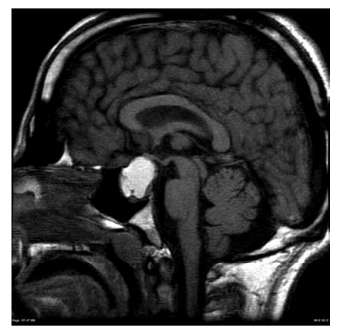

Mulher de 61 anos apresenta quadro de cefaleia progressiva há 5 meses, evoluindo com alteração da visão há 2 semanas. Uma ressonância magnética realizada há 2 dias é mostrada a seguir.